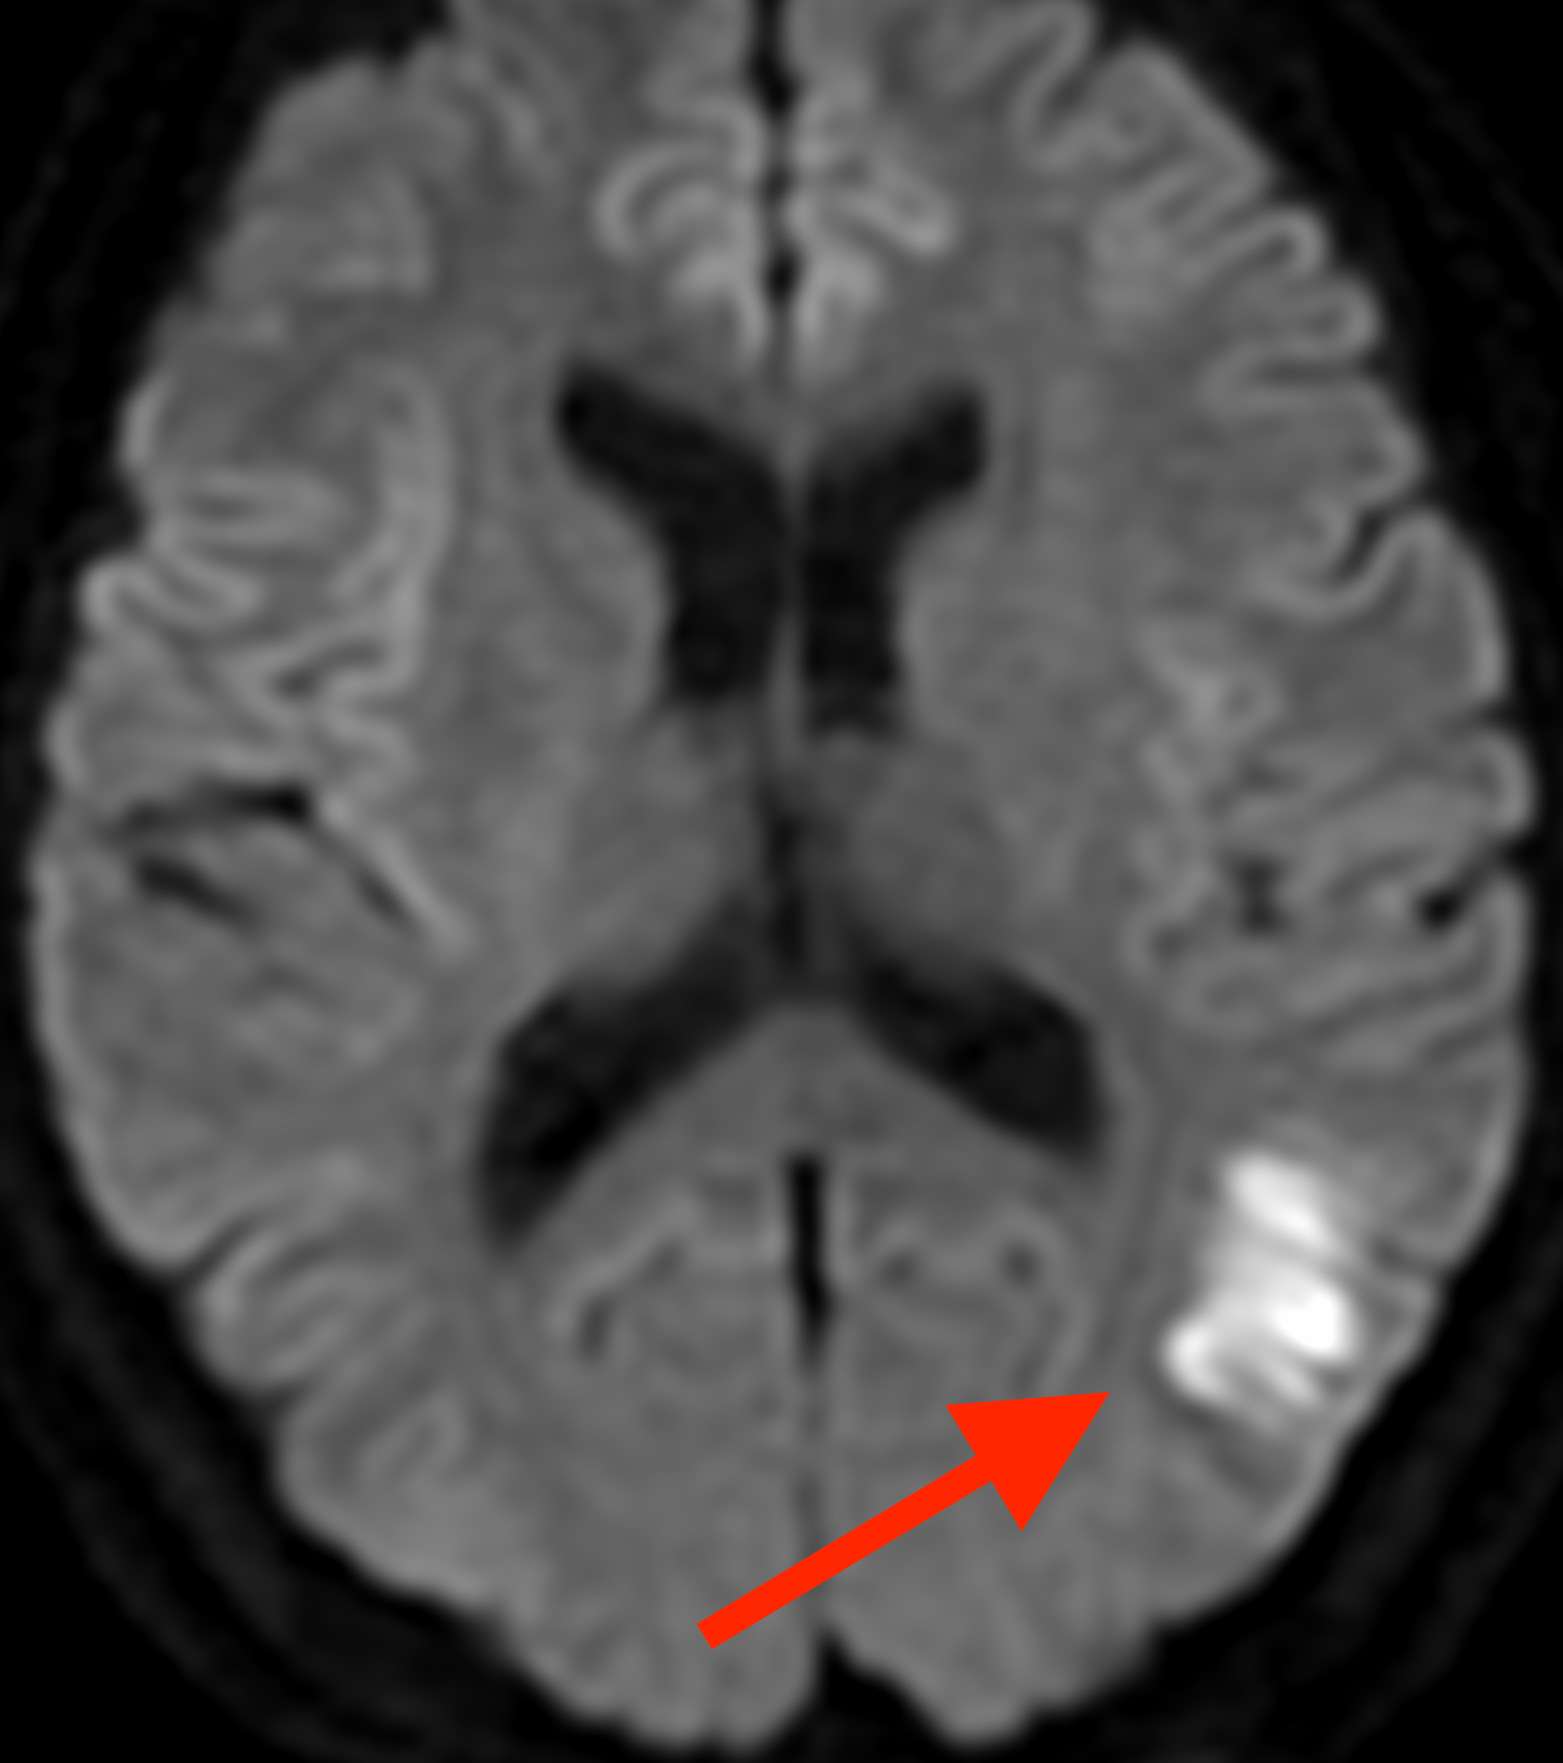

頭部MRI検査(拡散強調画像)を見ました。

片頭痛と脳梗塞

すると、左の後頭葉頭に脳梗塞を認めました。